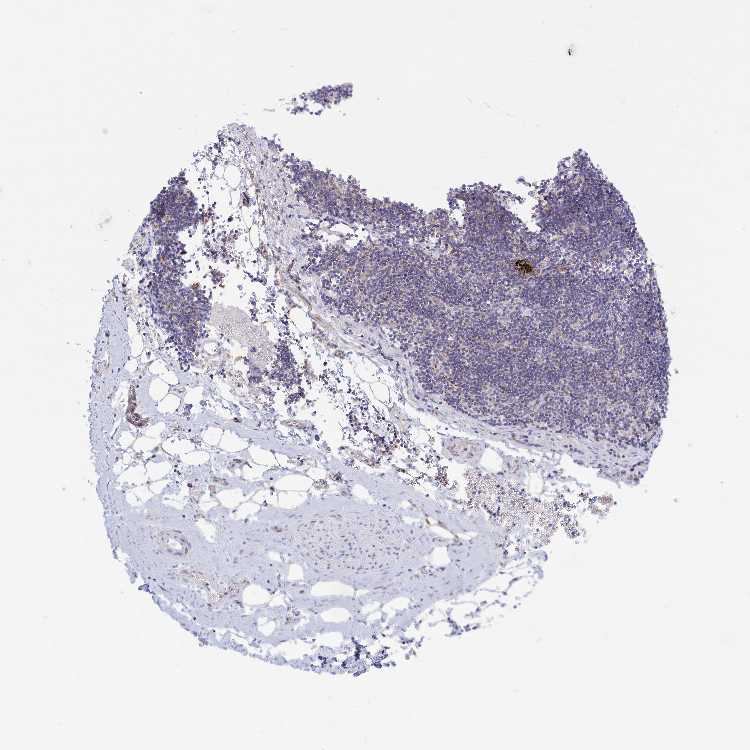

SOFT TISSUE 1 - Antibody stainingi

Antibody staining in the annotated cell types in the current human tissue is reported as not detected, low, medium, or high, based on conventional immunohistochemistry profiling in selected tissues. This score is based on the combination of the staining intensity and fraction of stained cells.

Each image is clickable and will lead to virtual microscopy that enables deeper exploration of all samples and also displays staining intensity scores, fraction scores and subcellular localization as well as patient and tissue information for each sample.

Antibody HPA043238

Fibroblasts Not detected

Peripheral nerve Not detected

SOFT TISSUE 2 - Antibody stainingi